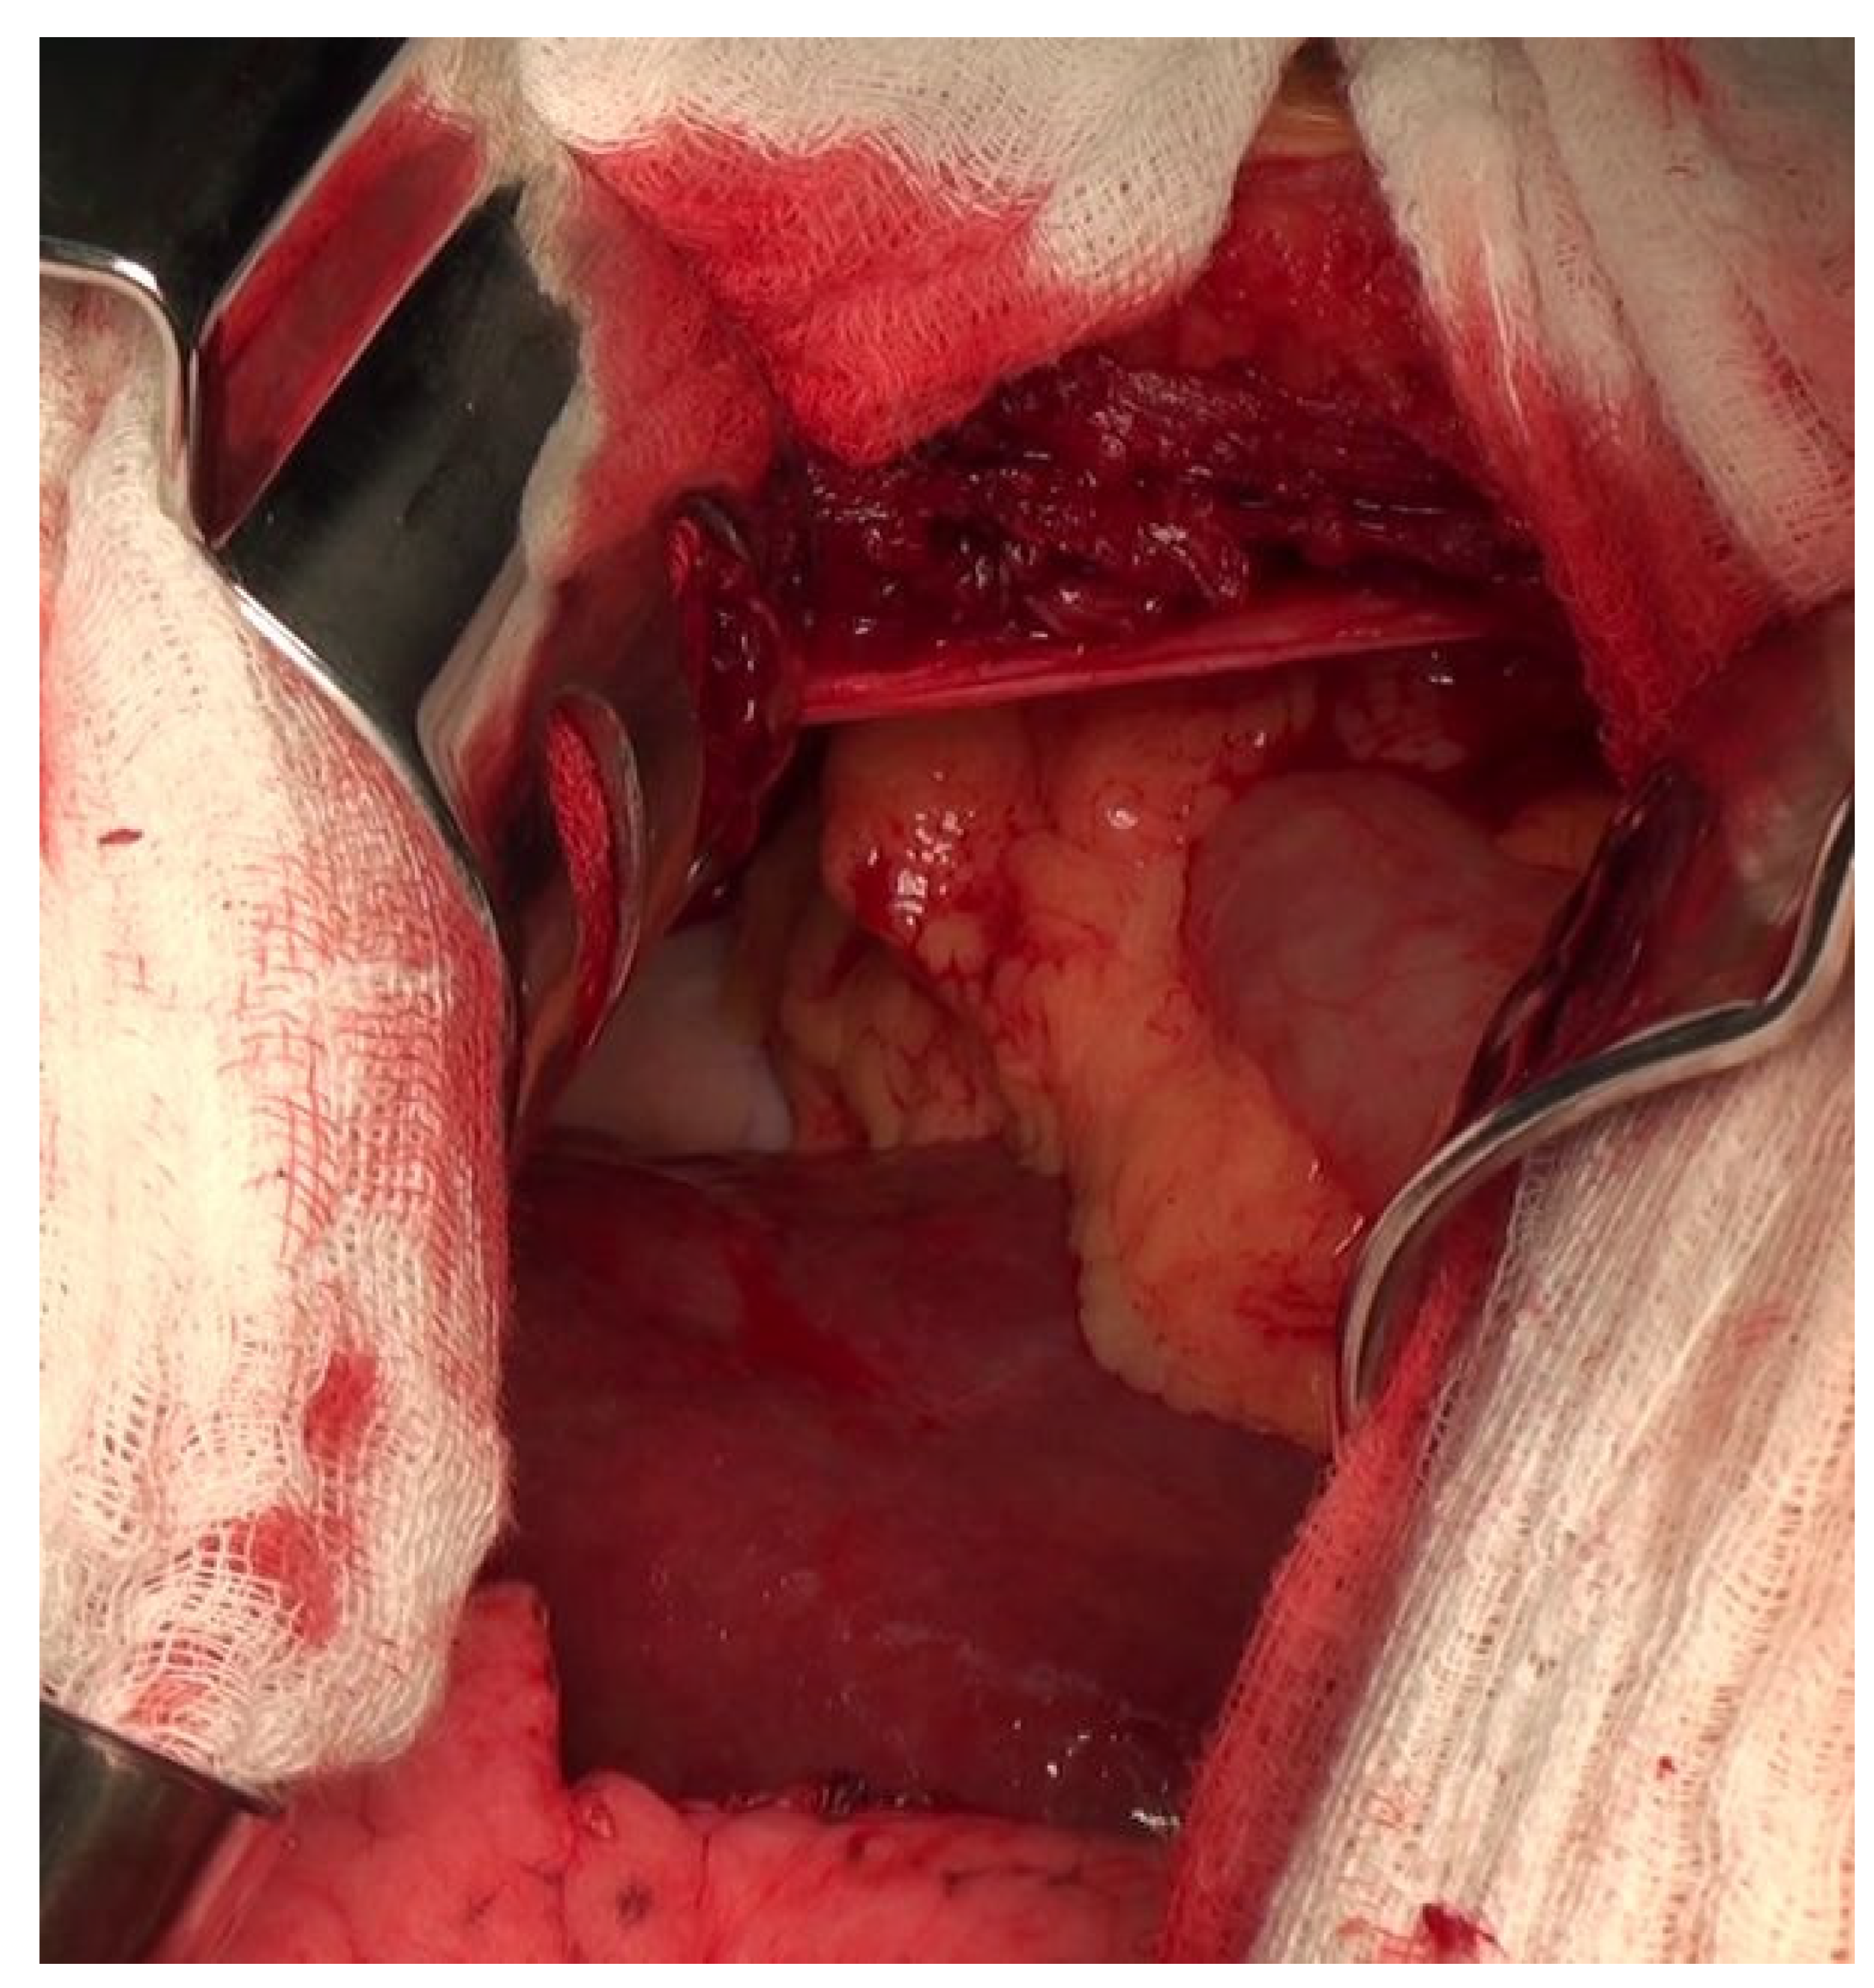

Diaphragmatic Liver Herniation after Radiofrequency Ablation of a Secondary Liver Tumor

Hoskovec, D.; Hořejš, J.; Krška, Z.; Argalácsová, S.; Klobušický, P. Diaphragmatic Liver Herniation after Radiofrequency Ablation of a Secondary Liver Tumor. Diagnostics 2024, 14, 26. https://doi.org/10.3390/diagnostics14010026